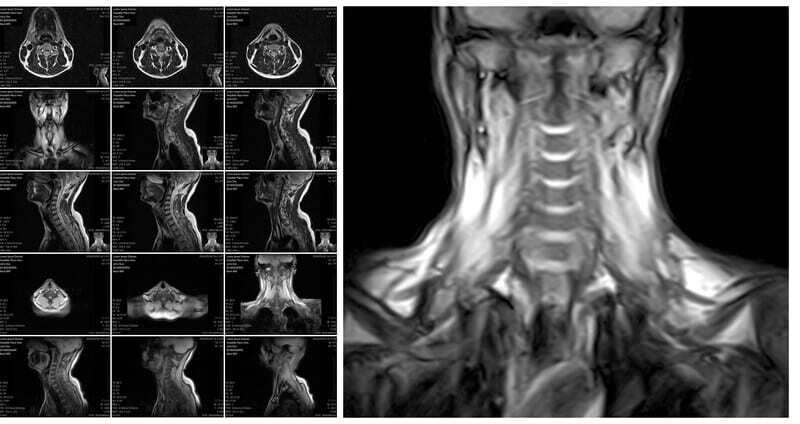

Chronic neck pain usually centers around the nerves. A disc in the neck can become herniated or “bulge” because of the wear and tear of the tendons, ligaments, and muscles.

Sometimes in an attempt to stabilize the weakened area of the neck, bone spurs will form (osteoarthritis) to “hold things in place.”

In our over 25 years of helping people with neck pain treatment in Los Angeles, we have been able to help patients with a diagnosis of: